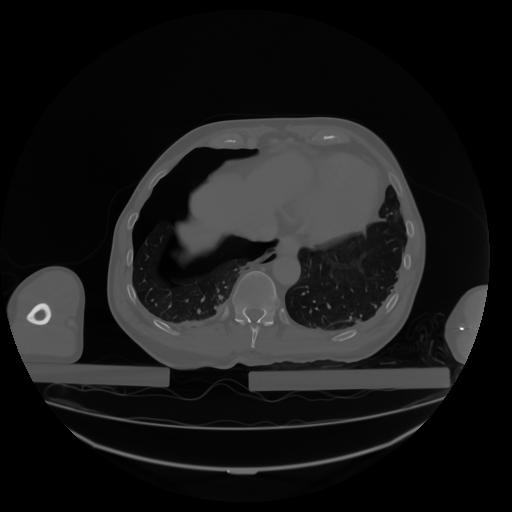

27 CUERPO,CE,Axial,3.0,CUERPO,,